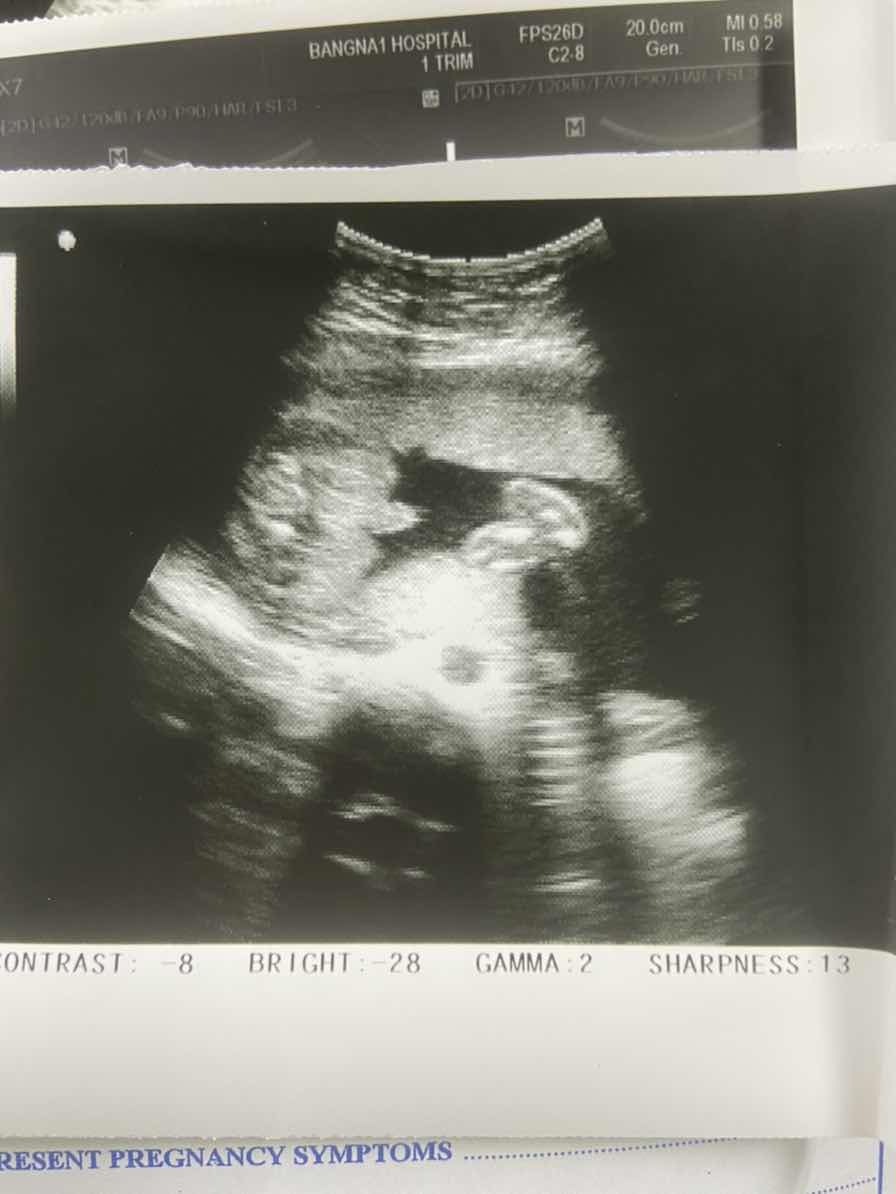

น้องออโต้#ใครมีประสบการณ์ กำหนดคลอด1ก.ค.64 แต่คลอดวันนี้6 มิ.ย.64เอาซะไม่ทันตั้งตัวเลยลูกออกก่อนกำหนดเยอะเกินนน.2530กรัม ไม่เหลืองไม่ต้องเข้าตู้อบคับ😀